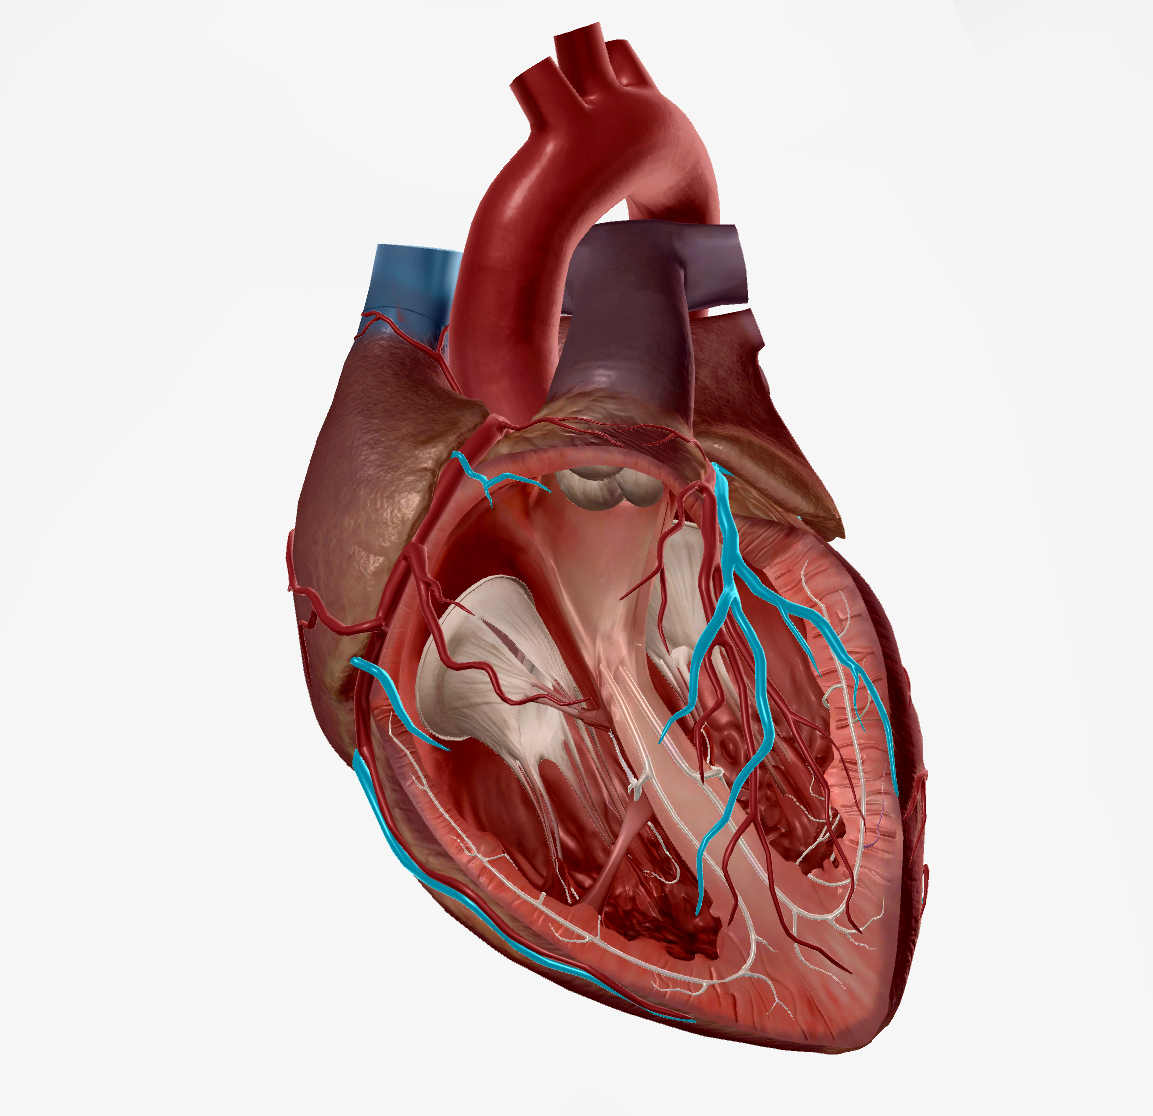

Left Ventricle

Right Ventricle

Tricuspid Valve

Bicuspid Valve

Aortic Valve

Papillary Muscle

Pulmonary Valve

Interventricular Septum

Chordae Tendineae

Anterior Interventricular Artery

Circumflex Branch

Coronary Artery

Middle Cardiac Vein

Coronary Sinus

Anterior Interventricular Sulcus

Interatrial Septum

Coronary Sulcus

Small Cardiac Vein

Anterior Cardiac Vein

Coronary Veins

Great Cardiac Vein